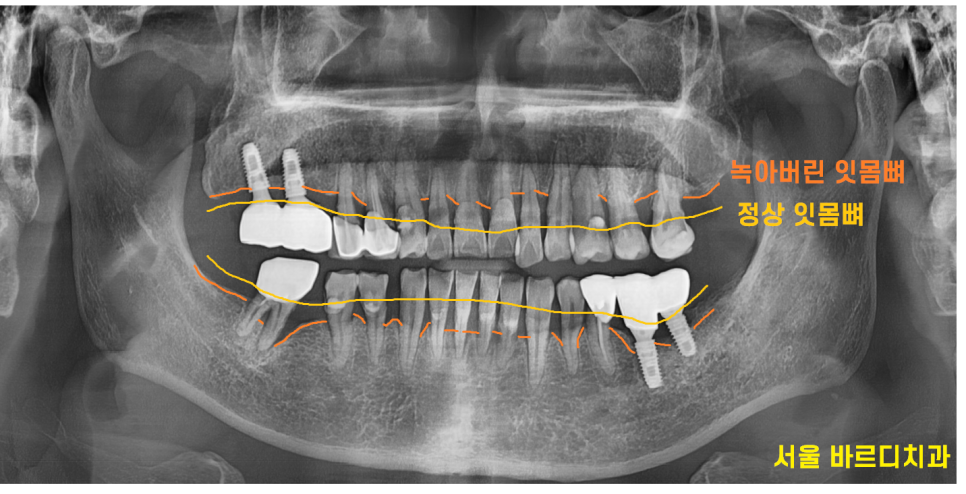

검사를 위해 찍어본 x ray

전형적인 풍치 증상입니다.

녹아버린 잇몸뼈로 치아가 흔들 흔들

길어 보이는 상황이었습니다.